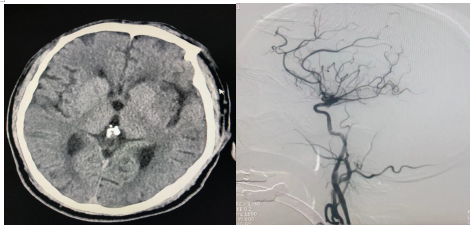

患者王某,男,59岁,平素健康状况良好,无吸烟、饮酒等不良嗜好。于入院前5小时突发意识障碍,呼之不应,工友立即拨打120,于2023年3月28日23:50送至我院急诊科。急查头颅CT未见明显出血。

图1:术前

值班医师在接诊后迅速对患者进行评估,相关查体:体温36.5 ℃,脉搏 70 次/分,呼吸 18 次/分,血压 125/78 mmHg,意识障碍,查体不能配合,双眼左侧凝视,双侧瞳孔等大等圆,直径1.5mm,光反射灵敏,四肢肌肉未见萎缩,左侧肢体肌力5级,右侧肢体肌力0级。左侧肢体肌张力正常。右侧肌张力减低,左侧babinski氏(+), 颈软, 无抵, Brudzinski's sign(-)。NIHSS评分19分,GCS:评分6分,发病前MRS评分0分。考虑大血管闭塞可能,因患者已超过静脉溶栓时间窗,结合患者相关查体及检查向患者家属交代病情,于次日00:30家属同意急诊介入治疗,我科迅速启动了急诊介入流程,2023年3月29日01:00在科主任田文生的指导下开启了急诊血管再通手术。